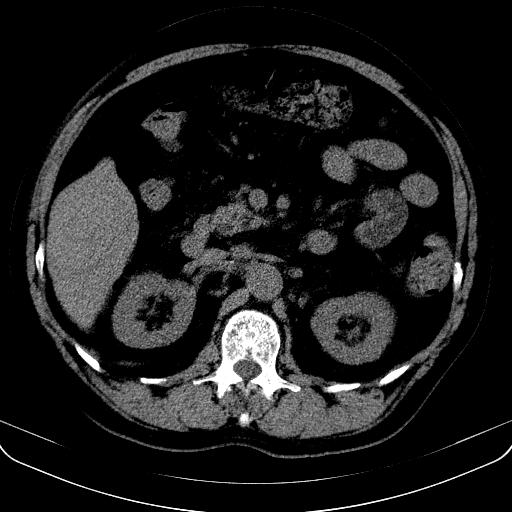

以下是引用jia119在2008-3-5 13:31:00的发言:[br]肝内多发片状低密度影,密度不均,我还是考虑肝ca可能,另肝内小囊肿,胆囊增大。

以下是引用形影不离在2008-3-5 12:18:00的发言:[br]肝硬化伴门脉高压征,肝内占位待排,增强再说.

以下是引用随光逐影在2008-3-5 21:11:00的发言:[br]肝硬化伴门脉高压(食管下段静脉曲张),肝癌不排除。建议:行ct增强扫描检查。

以下是引用同在2008-3-5 13:56:00的发言:[br]考虑肝癌可能性大,胆囊增大.